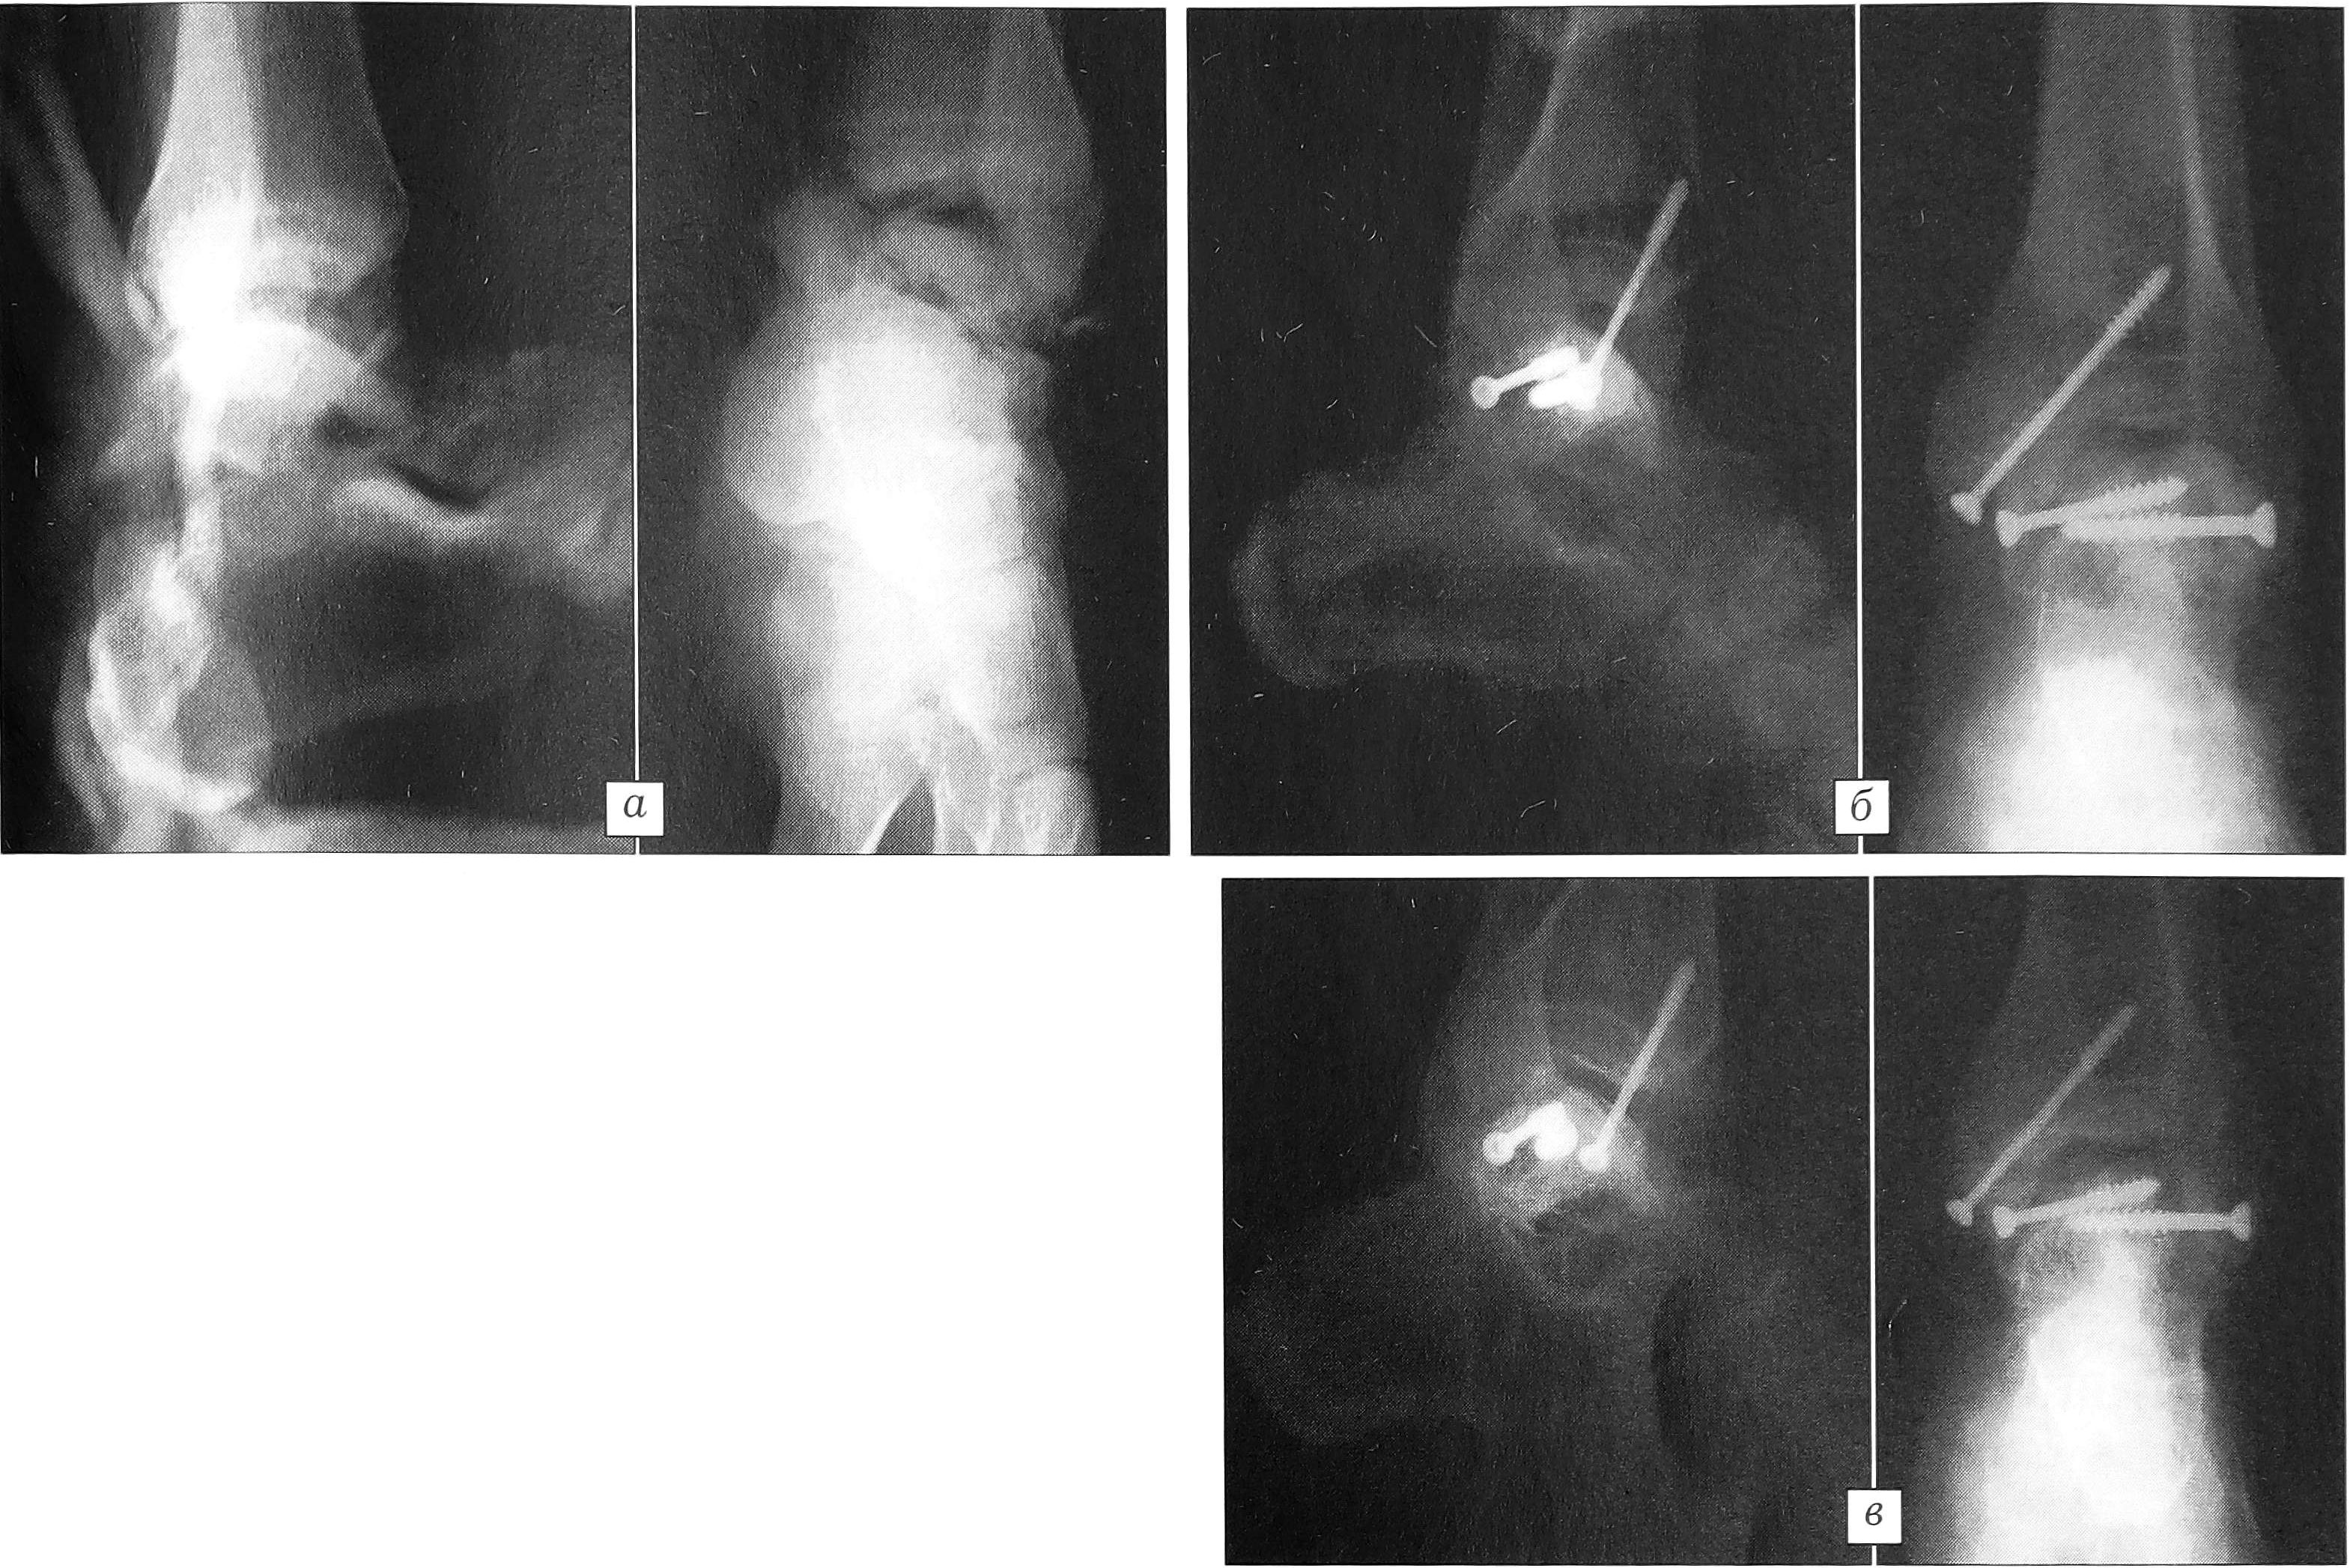

Пример 2. Больной В., 31 года, упал во время работы с высоты более 2 м. Диагноз: перелом шейки таранной кости правой стопы (рис. 2, а). Оперирован через 10 ч после травмы. Оперативный доступ с остеотомией внутренней лодыжки. При ревизии выявлен Ѵ-образный трехфрагментарный перелом тела и шейки таранной кости. Примечательно, что перелом тела обнаружен только при ревизии на операционном столе. Произведены открытая репозиция и фиксация винтами АО тела и шейки таранной кости (рис. 2, б). Послеоперационное течение без осложнений, заживление первичным натяжением. Нагрузка в функциональном туторе разрешена через 2 мес. Пациент приступил к труду без ограничений через 5 мес.

Рис. 2. Рентгенограммы больного В. а — при поступлении; б — после открытой репозиции и фиксации тела и шейки таранной кости винтами АО.

Пример 3. Больной Г., 34 лет, госпитализирован с диагнозом: автодорожная политравма — закрытая черепно-мозговая травма, ушиб головного мозга; перелом диафиза левого плеча со смещением отломков; открытый оскольчатый перелом шейки и блока левой таранной кости со смещением отломков, открытый перелом внутренней лодыжки слева (рис. 3, а). Операции в день госпитализации: интрамедуллярный остеосинтез левого плеча, первичная хирургическая обработка раны стопы, остеосинтез таранной кости и внутренней лодыжки винтами. Послеоперационная иммобилизация голеностопного сустава и стопы аппаратом АО (3 нед) и функциональным тутором с супинатором. Дозированно возрастающая нагрузка в туторе через 2 мес после операции. При контрольном осмотре через 3 мес выявлен пролапс и начинающийся асептический некроз части блока таранной кости (рис. 3, б). Проведен курс лечения антикоагулянтами, дезагрегантами, препаратами, улучшающими реологические свойства крови. Физические нагрузки снижены, рекомендованы плавание, занятия на тренажере, массаж. При контрольном осмотре через 1 мес отмечены уменьшение зоны некроза, сохраняющаяся контрактура голеностопного сустава (рис. 3, в). Металлоконструкции удалены через 6 мес, пациент приступил к работе по специальности.

Рис. 3. Рентгенограммы больного Г. а — при поступлении; б — при контрольном осмотре через 3 мес: определяется пролапс и начинающийся асептический некроз части блока таранной кости; в — после курса интенсивной сосудистой терапии.